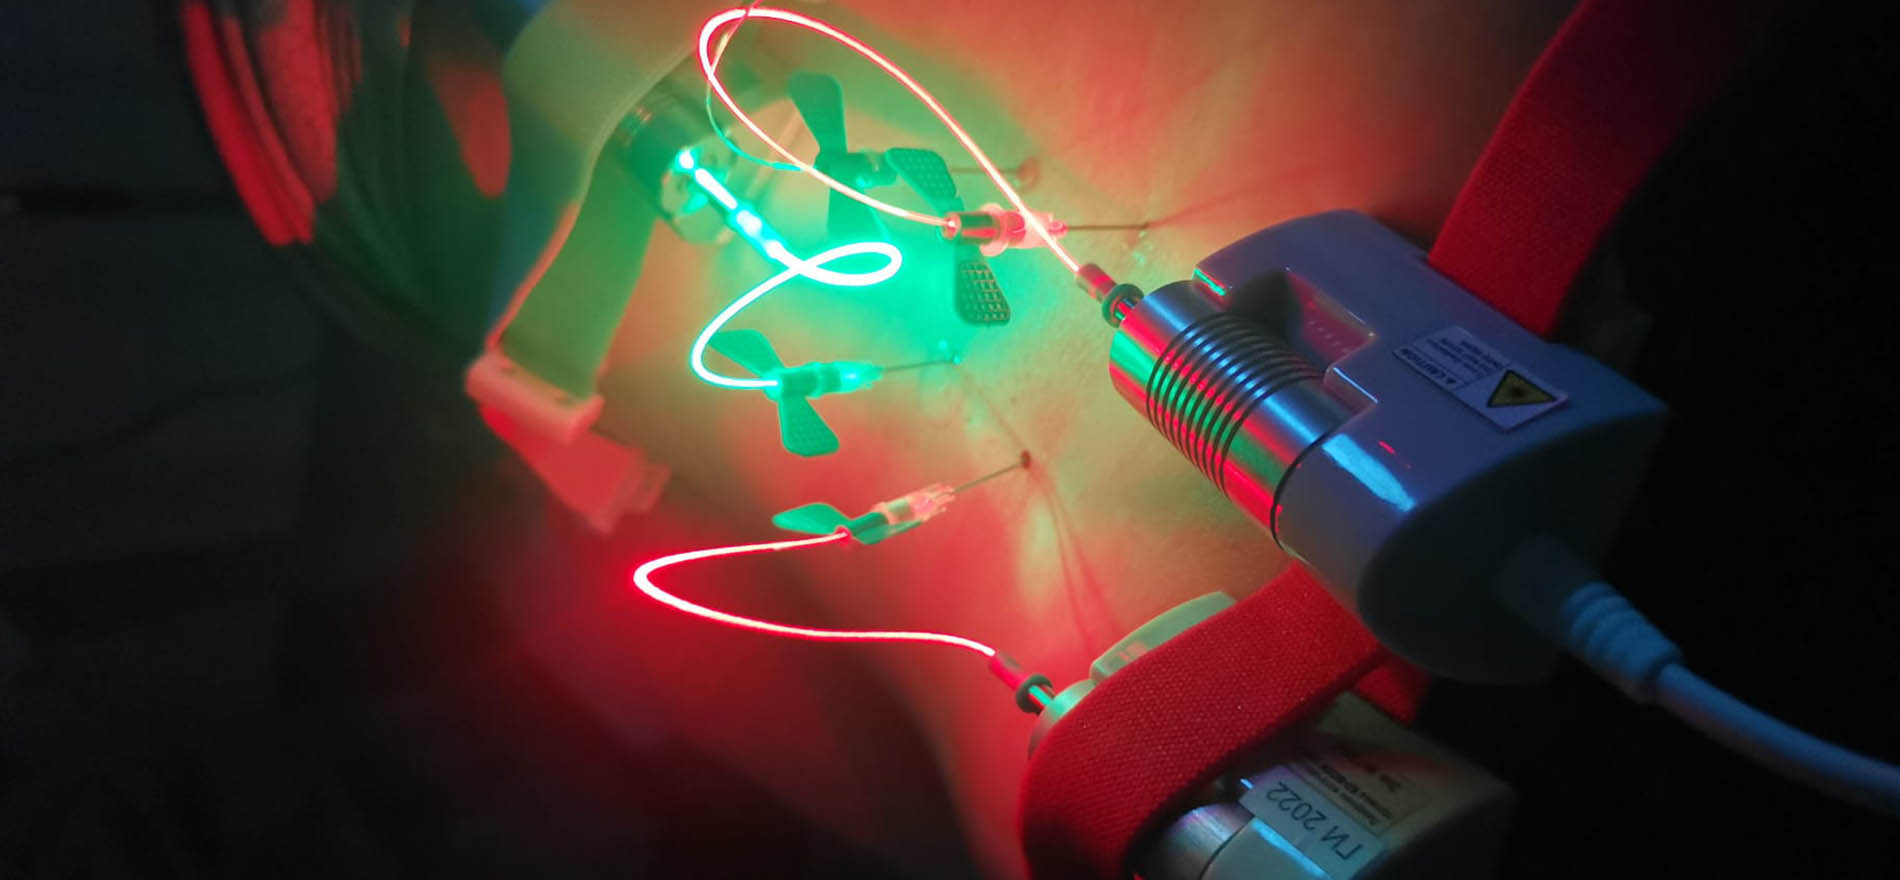

Plasma Rico en Plaquetas (PRP) + Láser

Clínica pionera en el tratamiento combinado